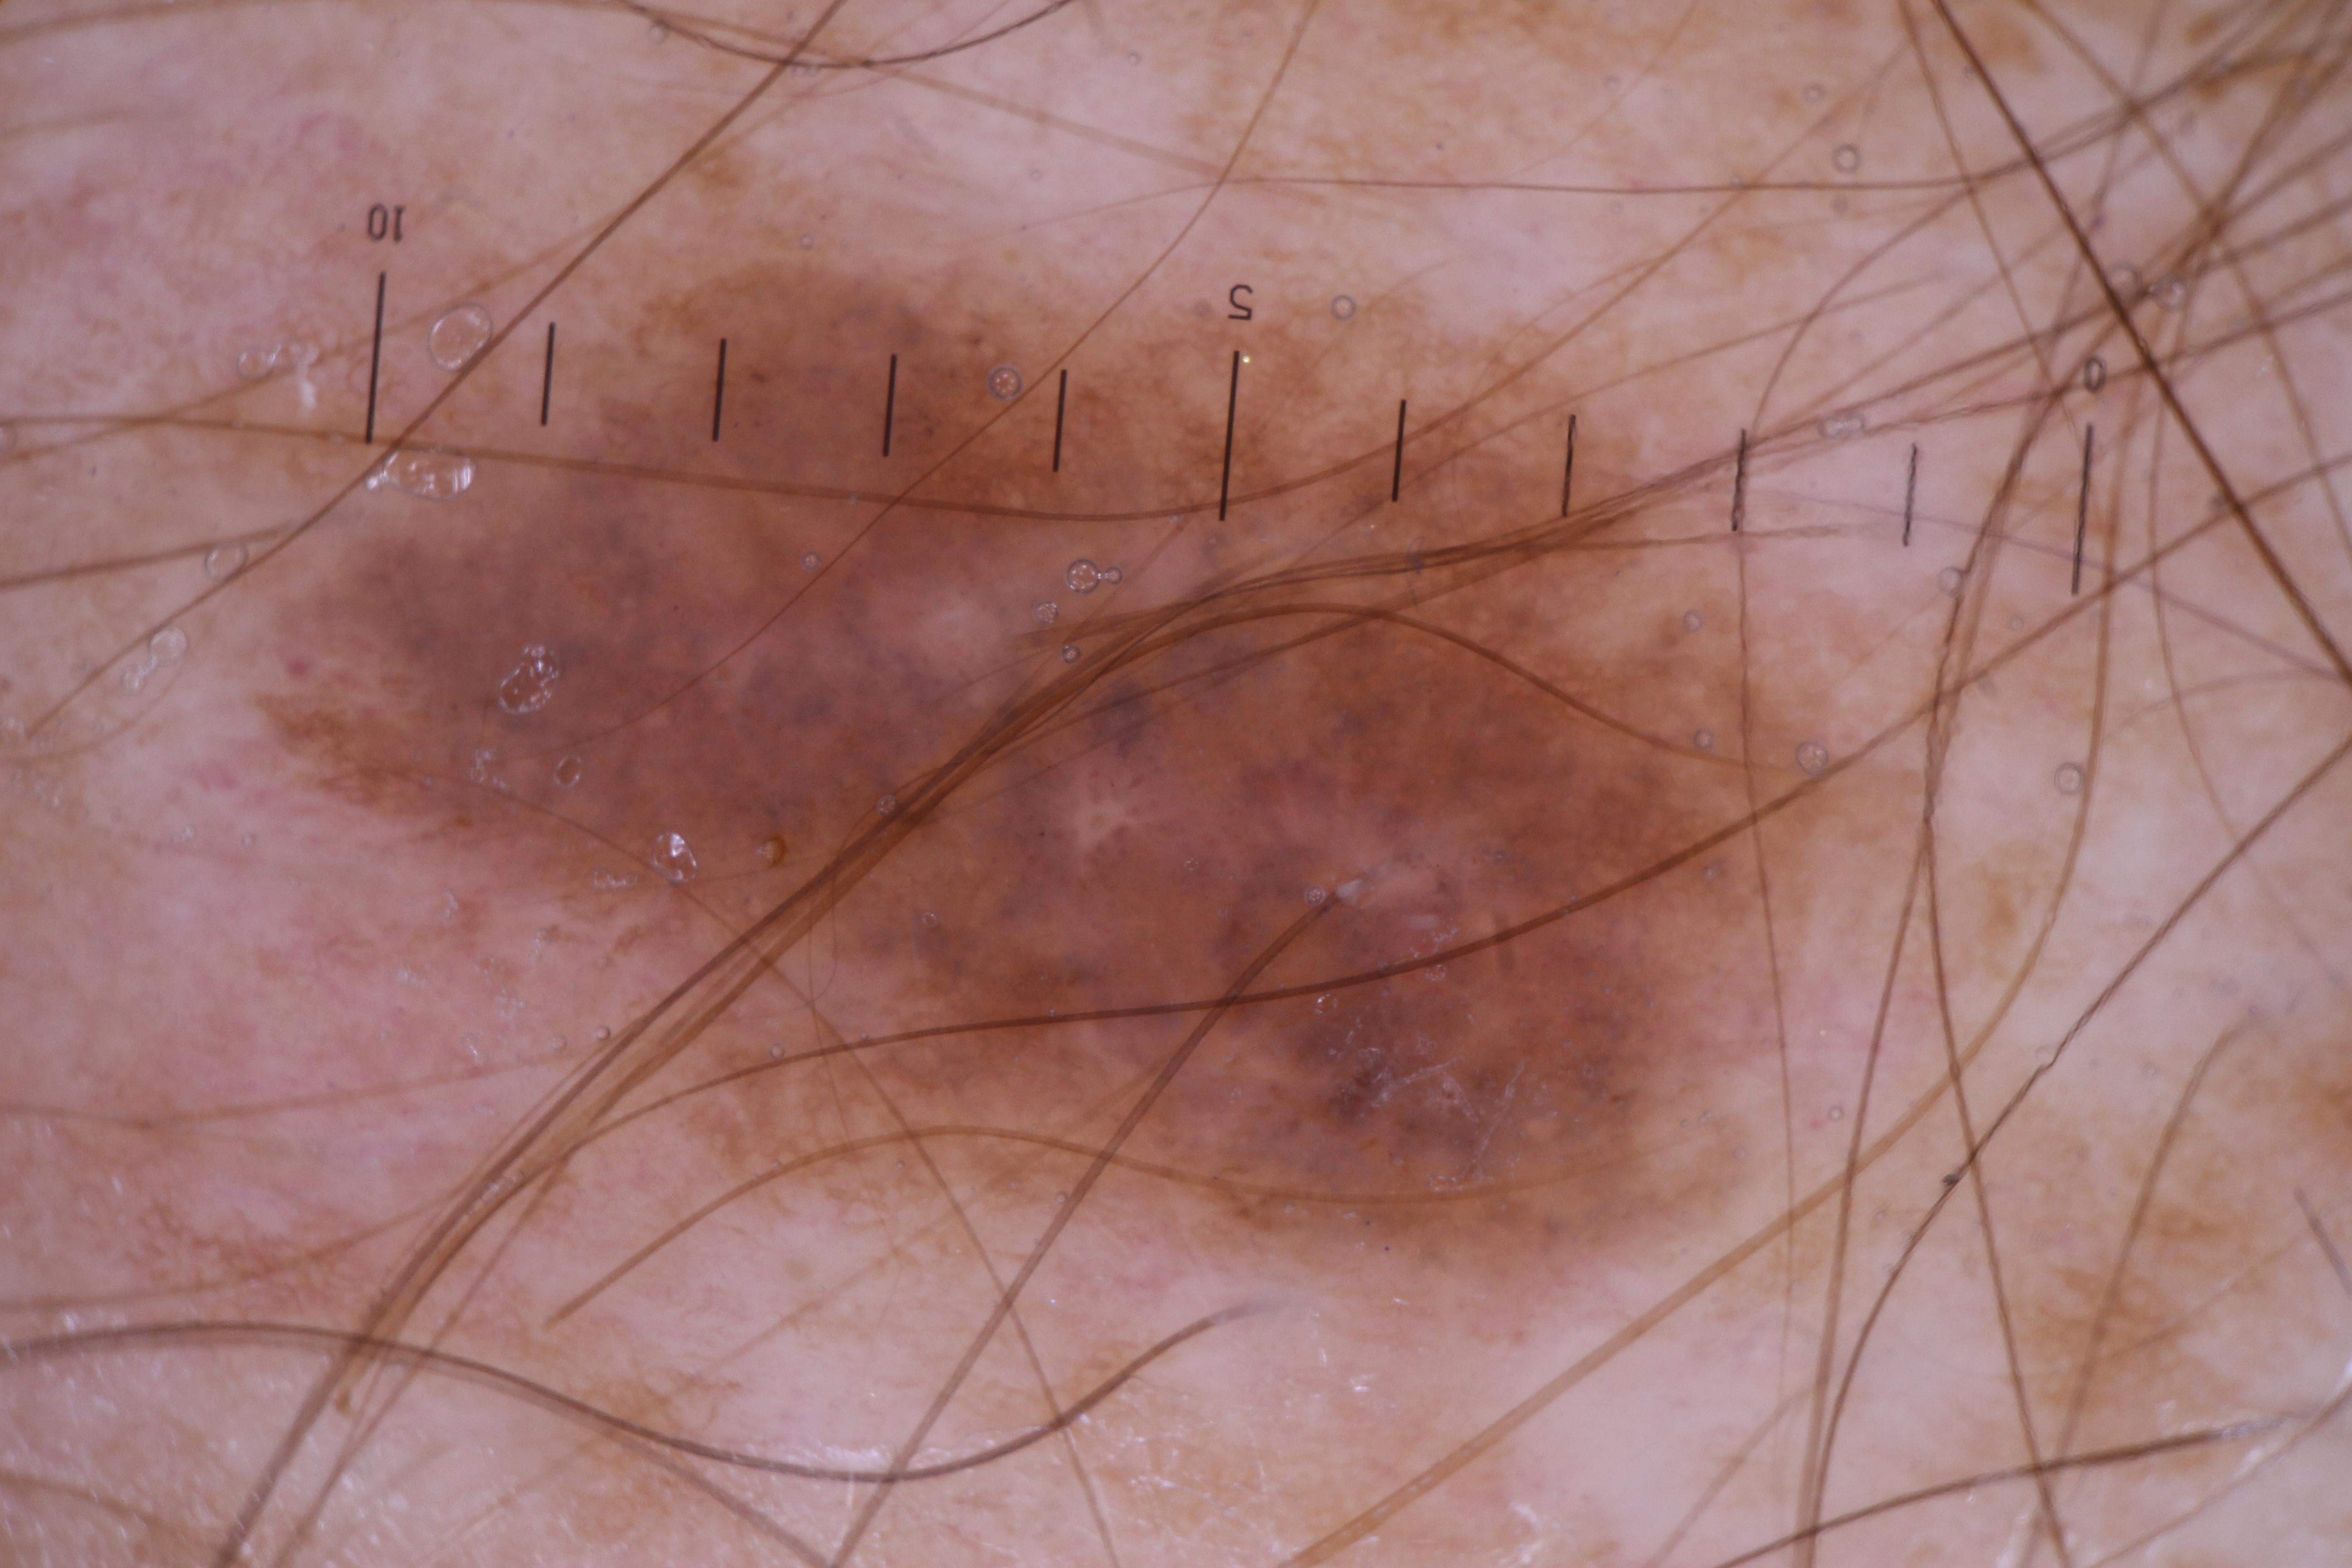

{

"age_approx": 70,

"anatom_site_general": "anterior torso",

"concomitant_biopsy": true,

"diagnosis_1": "Malignant",

"diagnosis_2": "Malignant melanocytic proliferations (Melanoma)",

"diagnosis_3": "Melanoma, NOS",

"diagnosis_confirm_type": "histopathology",

"fitzpatrick_skin_type": "II",

"image_type": "dermoscopic",

"lesion_id": "IL_2700215",

"melanocytic": true,

"patient_id": "IP_8502723",

"sex": "male"

}